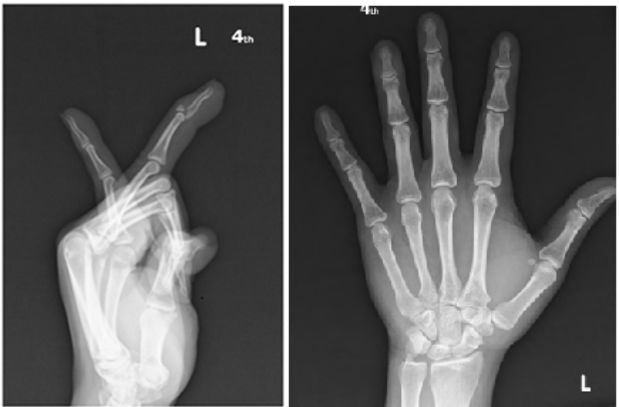

54 45歲男性接球不慎頂到左手無名指,當下疼痛明顯,無名指無法完全伸直,今天求診,X光檢查如附 圖所示,下列敘述何者正確?①X光顯示左手無名指末端指節撕脫性骨折 ②左無名指日久失治外觀 會呈現錘狀指 ③此受傷機轉主要由於屈指淺肌的拉扯所致 ④使用夾板固定時,左手無名指遠端 指節需呈現些微屈曲(flexion)位做固定 (A)①② (B)①④ (C)①③④ (D)②③④